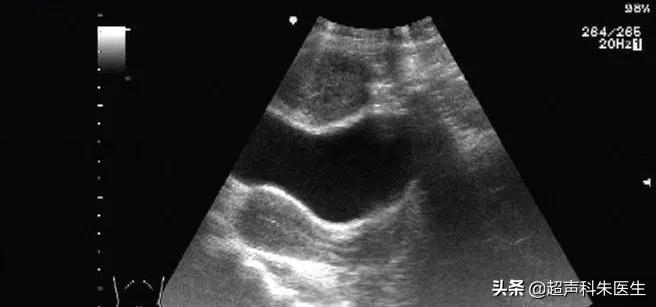

上图显示包块、膀胱、子宫附件的关系

通过动态观察,可见包块位于腹膜外,与腹直肌分界不清,具体关系如上图所示

超声所见:下腹部腹膜外探及一低回声团块,大小12.4*6.9*9.0cm,边界清楚,内部回声不均质,内见散在点状强回声及小片状无回声区,包块与腹直肌分界不清,CDFI观察:其内可见少量血流信号。